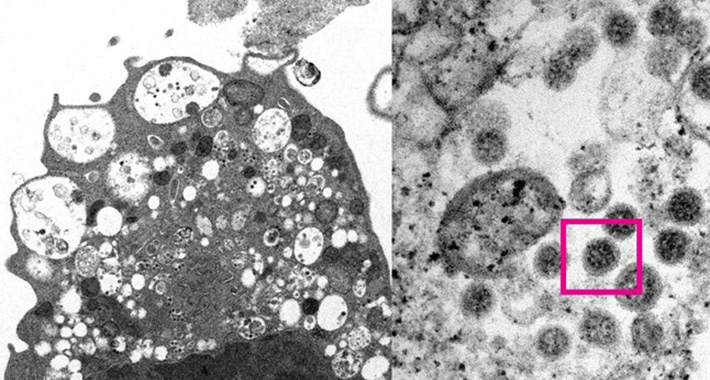

To je dijelom rezultat imunološke zaštite cijepljenjem među osobama starijim od 5 godina, boostera, kao i potencijalno niže virulencije samog virusa, navodi se u izvještaju. Druge studije sugerirale su da je varijanta manje sposobna prodrijeti duboko u pluća.